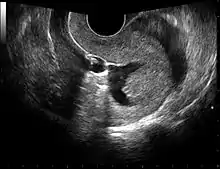

Left hydrosalpinx on gynecologic ultrasonography

The examination can be performed by transabdominal ultrasonography, generally with a full bladder which acts as an acoustic window to achieve better visualization of pelvis organs, or by transvaginal ultrasonography with a specifically designed vaginal transducer. Transvaginal imaging utilizes a higher frequency imaging, which gives better resolution of the ovaries, uterus and endometrium (the fallopian tubes are generally not seen unless distended), but is limited to depth of image penetration, whereas larger lesions reaching into the abdomen are better seen transabdominally. Having a full bladder for the transabdominal portion of the exam is helpful because sound travels through fluid with less attenuation to better visualize the uterus and ovaries which lies posteriorly to the bladder. The procedure is by definition invasive when performed transvaginally. Scans are performed by health care professionals called sonographers, or gynecologists trained in ultrasound.